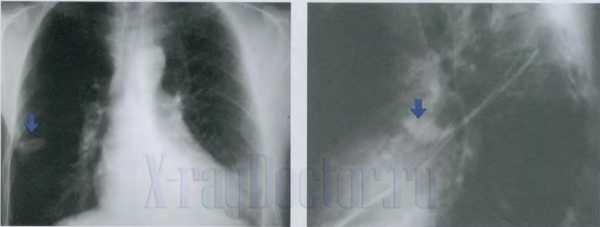

Π€ΠΎΡΠΎ ΡΠ΅Π½ΡΠ³Π΅Π½Π° ΡΠ°ΠΊΠ° Π»Π΅Π³ΠΊΠΈΡΠ Π΅Π½ΡΠ³Π΅Π½ΠΎΠ³ΡΠ°ΠΌΠΌΡ: ΠΏΠ΅ΡΠΈΡΠ΅ΡΠΈΡΠ΅ΡΠΊΠΎΠ΅ ΠΎΠ±ΡΠ°Π·ΠΎΠ²Π°Π½ΠΈΠ΅ ΠΏΡΠ°Π²ΠΎΠ³ΠΎ Π»Π΅Π³ΠΊΠΎΠ³ΠΎ Π½Π° ΠΏΡΡΠΌΠΎΠΌ ΠΈ Π±ΠΎΠΊΠΎΠ²ΠΎΠΌ ΡΠ½ΠΈΠΌΠΊΠ°Ρ (Π° ΠΈ Π±). ΠΠΎΠ΄ΡΡΠ³ΠΈΠ²Π°Π½ΠΈΠ΅ ΠΏΡΠ°Π²ΠΎΠ³ΠΎ ΠΊΡΠΏΠΎΠ»Π° Π΄ΠΈΠ°ΡΡΠ°Π³ΠΌΡ ΠΈ ΠΏΠ»Π΅Π²ΡΠ°Π»ΡΠ½ΡΠ΅ Π½Π°Π»ΠΎΠΆΠ΅Π½ΠΈΡ ΡΠΏΡΠ°Π²Π° ΠΏΡΠΈ ΠΌΠ΅Π·ΠΎΡΠ΅Π»ΠΈΠΎΠΌΠ΅ (Π²).

ΠΠ½Π°Π»ΠΈΠ·ΠΈΡΡΡ ΡΠΎΡΠΎ ΡΠ΅Π½ΡΠ³Π΅Π½ΠΎΠ³ΡΠ°ΠΌΠΌ ΠΏΡΠΈ ΠΏΠ΅ΡΠΈΡΠ΅ΡΠΈΡΠ΅ΡΠΊΠΎΠΌ ΡΠ°ΠΊΠ΅ Π»Π΅Π³ΠΊΠΎΠ³ΠΎ Π² ΠΏΡΡΠΌΠΎΠΉ ΠΈ Π±ΠΎΠΊΠΎΠ²ΠΎΠΉ ΠΏΡΠΎΠ΅ΠΊΡΠΈΡΡ , ΠΏΡΠΎΡΠ»Π΅ΠΆΠΈΠ²Π°Π΅ΡΡΡ Π»ΡΡΠΈΡΡΡΠΉ ΠΊΠΎΠ½ΡΡΡ Π²ΠΎΠΊΡΡΠ³ ΠΏΠΎΠ»ΠΎΡΡΠ½ΠΎΠ³ΠΎ ΠΎΠ±ΡΠ°Π·ΠΎΠ²Π°Π½ΠΈΡ Π² ΠΏΡΠΎΠ΅ΠΊΡΠΈΠΈ Π»Π΅Π²ΠΎΠ³ΠΎ ΠΊΠΎΡΠ½Ρ. ΠΠ½ ΠΎΡΡΠ°ΠΆΠ°Π΅Ρ Π²ΡΡΠΎΠΊΡΡ Π²Π΅ΡΠΎΡΡΠ½ΠΎΡΡΡ ΠΏΠ΅ΡΠΈΡΠ΅ΡΠΈΡΠ΅ΡΠΊΠΎΠ³ΠΎΒ ΡΠ°ΠΊΠ° S5 ΡΡΠ΅Π΄Π½Π΅ΠΉ Π΄ΠΎΠ»ΠΈ ΠΏΡΠ°Π²ΠΎΠ³ΠΎ Π»Π΅Π³ΠΊΠΎΠ³ΠΎ.

ΠΠΎΠ»ΠΎΡΡΡ ΡΠ°ΡΠΏΠ°Π΄Π° ΡΠ»Π΅Π²Π° Π½Π΅ ΡΠ²Π»ΡΠ΅ΡΡΡ ΠΌΠ΅ΡΠ°ΡΡΠ°Π·ΠΎΠΌ. ΠΠ½Π° ΠΎΠ±ΡΠ°Π·ΠΎΠ²Π°Π½Π° ΠΏΡΠΎΠ½ΠΈΠΊΠ½ΠΎΠ²Π΅Π½ΠΈΠ΅ΠΌ ΡΠ°ΠΊΠΎΠ²ΠΎΠ³ΠΎ ΡΠ·Π»Π° Π² ΡΡΠ΅Π΄ΠΎΡΡΠ΅Π½ΠΈΡ. ΠΠ° ΠΎΡΡΡΡΡΡΠ²ΠΈΠ΅ ΠΌΠ΅ΡΠ°ΡΡΠ°Π·Π° ΡΠΊΠ°Π·ΡΠ²Π°Π΅Ρ Π½Π΅ΠΆΠ½ΡΠΉ Π²Π΅Π½ΡΠΈΠΊ Π²ΠΎΠΊΡΡΠ³ ΠΏΠΎΠ»ΠΎΡΡΠΈ ΡΠ°ΡΠΏΠ°Π΄Π° (ΡΠΊΠ°Π·Π°Π½ ΡΡΡΠ΅Π»ΠΊΠΎΠΉ).

Π Π΅Π½ΡΠ³Π΅Π½ΠΎΠ³ΡΠ°ΠΌΠΌΠ° Ρ Π½Π΅Π±ΠΎΠ»ΡΡΠΈΠΌ ΠΎΡΠ°Π³ΠΎΠΌ Π² ΠΏΡΡΠΌΠΎΠΉ ΠΏΡΠΎΠ΅ΠΊΡΠΈΠΈ. ΠΡΠΈ Π²ΡΠΏΠΎΠ»Π½Π΅Π½ΠΈΠΈ ΠΏΡΠ°Π²ΠΎΠΉ Π±ΠΎΠΊΠΎΠ²ΠΎΠΉ ΡΠ΅Π½ΡΠ³Π΅Π½ΠΎΠ³ΡΠ°ΡΠΈΠΈ ΡΠ΅ΡΠΊΠΎ Π²ΠΈΠ΄Π½Π° Π»ΠΎΠΊΠ°Π»ΠΈΠ·Π°ΡΠΈΡ ΠΏΠ°ΡΠΎΠ»ΠΎΠ³ΠΈΡΠ΅ΡΠΊΠΎΠ³ΠΎ ΠΎΠ±ΡΠ°Π·ΠΎΠ²Π°Π½ΠΈΡ Π² S4.